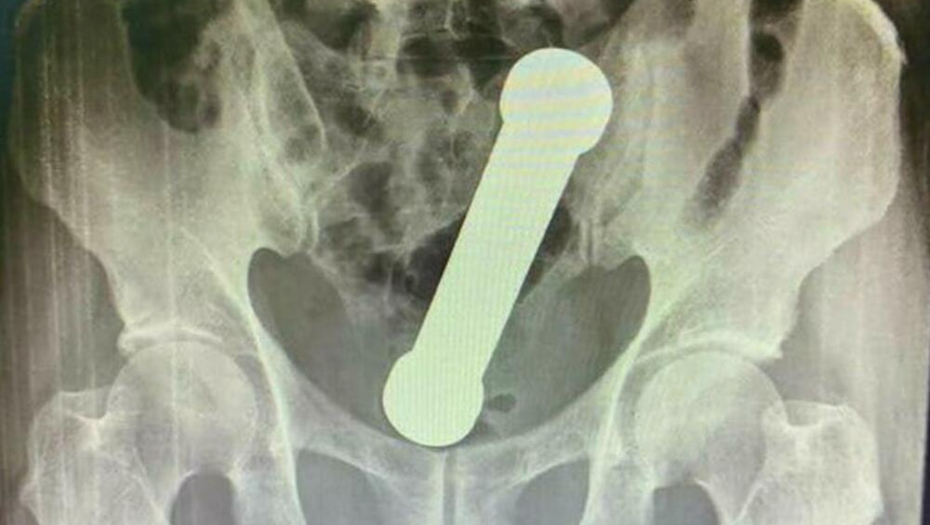

TEG OD 2 KG U REKTUMU Žalio se na bolove u stomaku, a kada su lekari videli rendgenski snimak nisu mogli da veruju!

Neidentifikovani 54-godišnjak je čekao dva dana pre nego što je zatražio medicinsku pomoć pošto nije uspeo da sam izvuče metalni teg težine 2 kilograma.

On se pojavio u bolnici u Manausu požalivši se na bolove u stomaku, mučninu i zatvor. Nakon rektalnog pregleda, lekari nisu mogli da pronađu uzrok njegovih problema pa su zatražili rendgenski snimak abdomena.

Foto: Printscreen

Rendgen je otkrio da je teg dugačak skoro 20 centimetara zaglavljen na mestu gde se debelo crevo spaja sa rektumom.